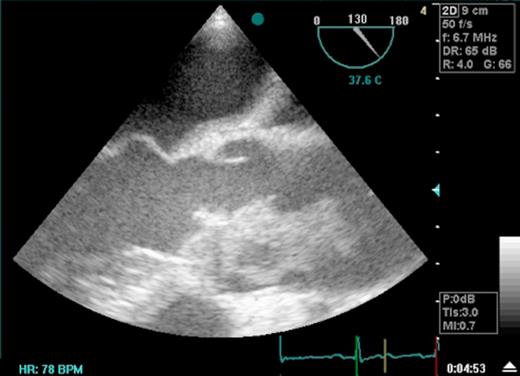

He was taken to theatre as an emergency. A pre-operative Transoesophageal Echocardiogram (TOE) confirmed the presence of thrombus on the aortic valve extending into the ascending aorta (Fig 1). After median sternotomy and initiation of cardiopulmonary bypass the ascending aorta was clamped at the level of the innominate artery. TOE confirmed that the clamp site was above the top level of the thrombus. The thrombus was all removed and submitted for bacteriological culture. Once the coronary ostia were identified the heart was arrested with cold blood cardioplegia. A calcified bicuspid aortic valve was excised and replaced with a 27-mm ATS open pivot heart valve. No organisms were seen on gram staining of the thrombus however following advice from the microbiological team empirical therapy with vancomycin and gentamicin was initiated. He made an uneventful postoperative recovery and was commenced on intravenous heparin after surgery until he was adequately anticoagulated with warfarin and aspirin. All cultures were negative. He was discharged from hospital on his eighth post-operative day.

Transoesophageal Echocardiogram depicting thrombus in the ascending aorta